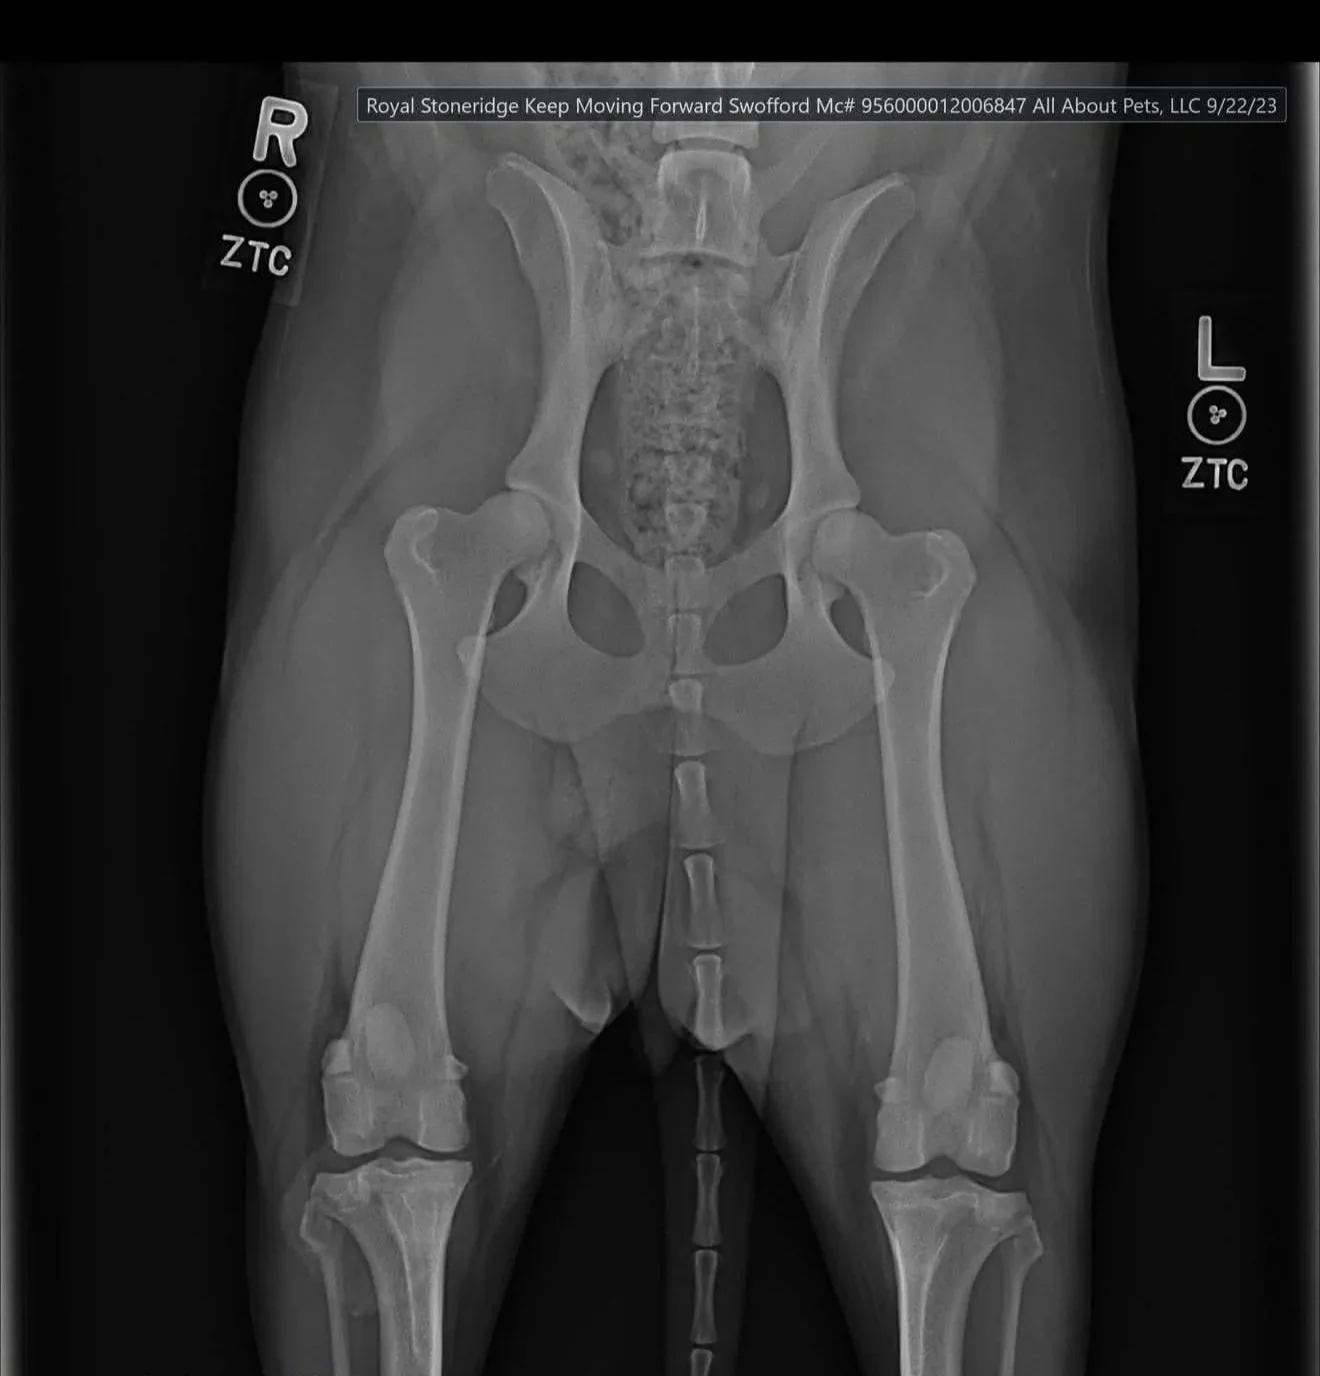

Screening: Available in two common forms in the U.S.: OFA and PennHIP, both of which use radiographs (x-rays) to measure the conformation and risk factors of the hips for dysplasia using a variety of measurements such as conformation evaluations and degree of laxity in the joint (In other terms, how well the joints are formed and if there is any space or flexibility in the joint that should not be there)

OFA Hip Grade Details

OFA Hip Evaluations are usually the most common used in the United States